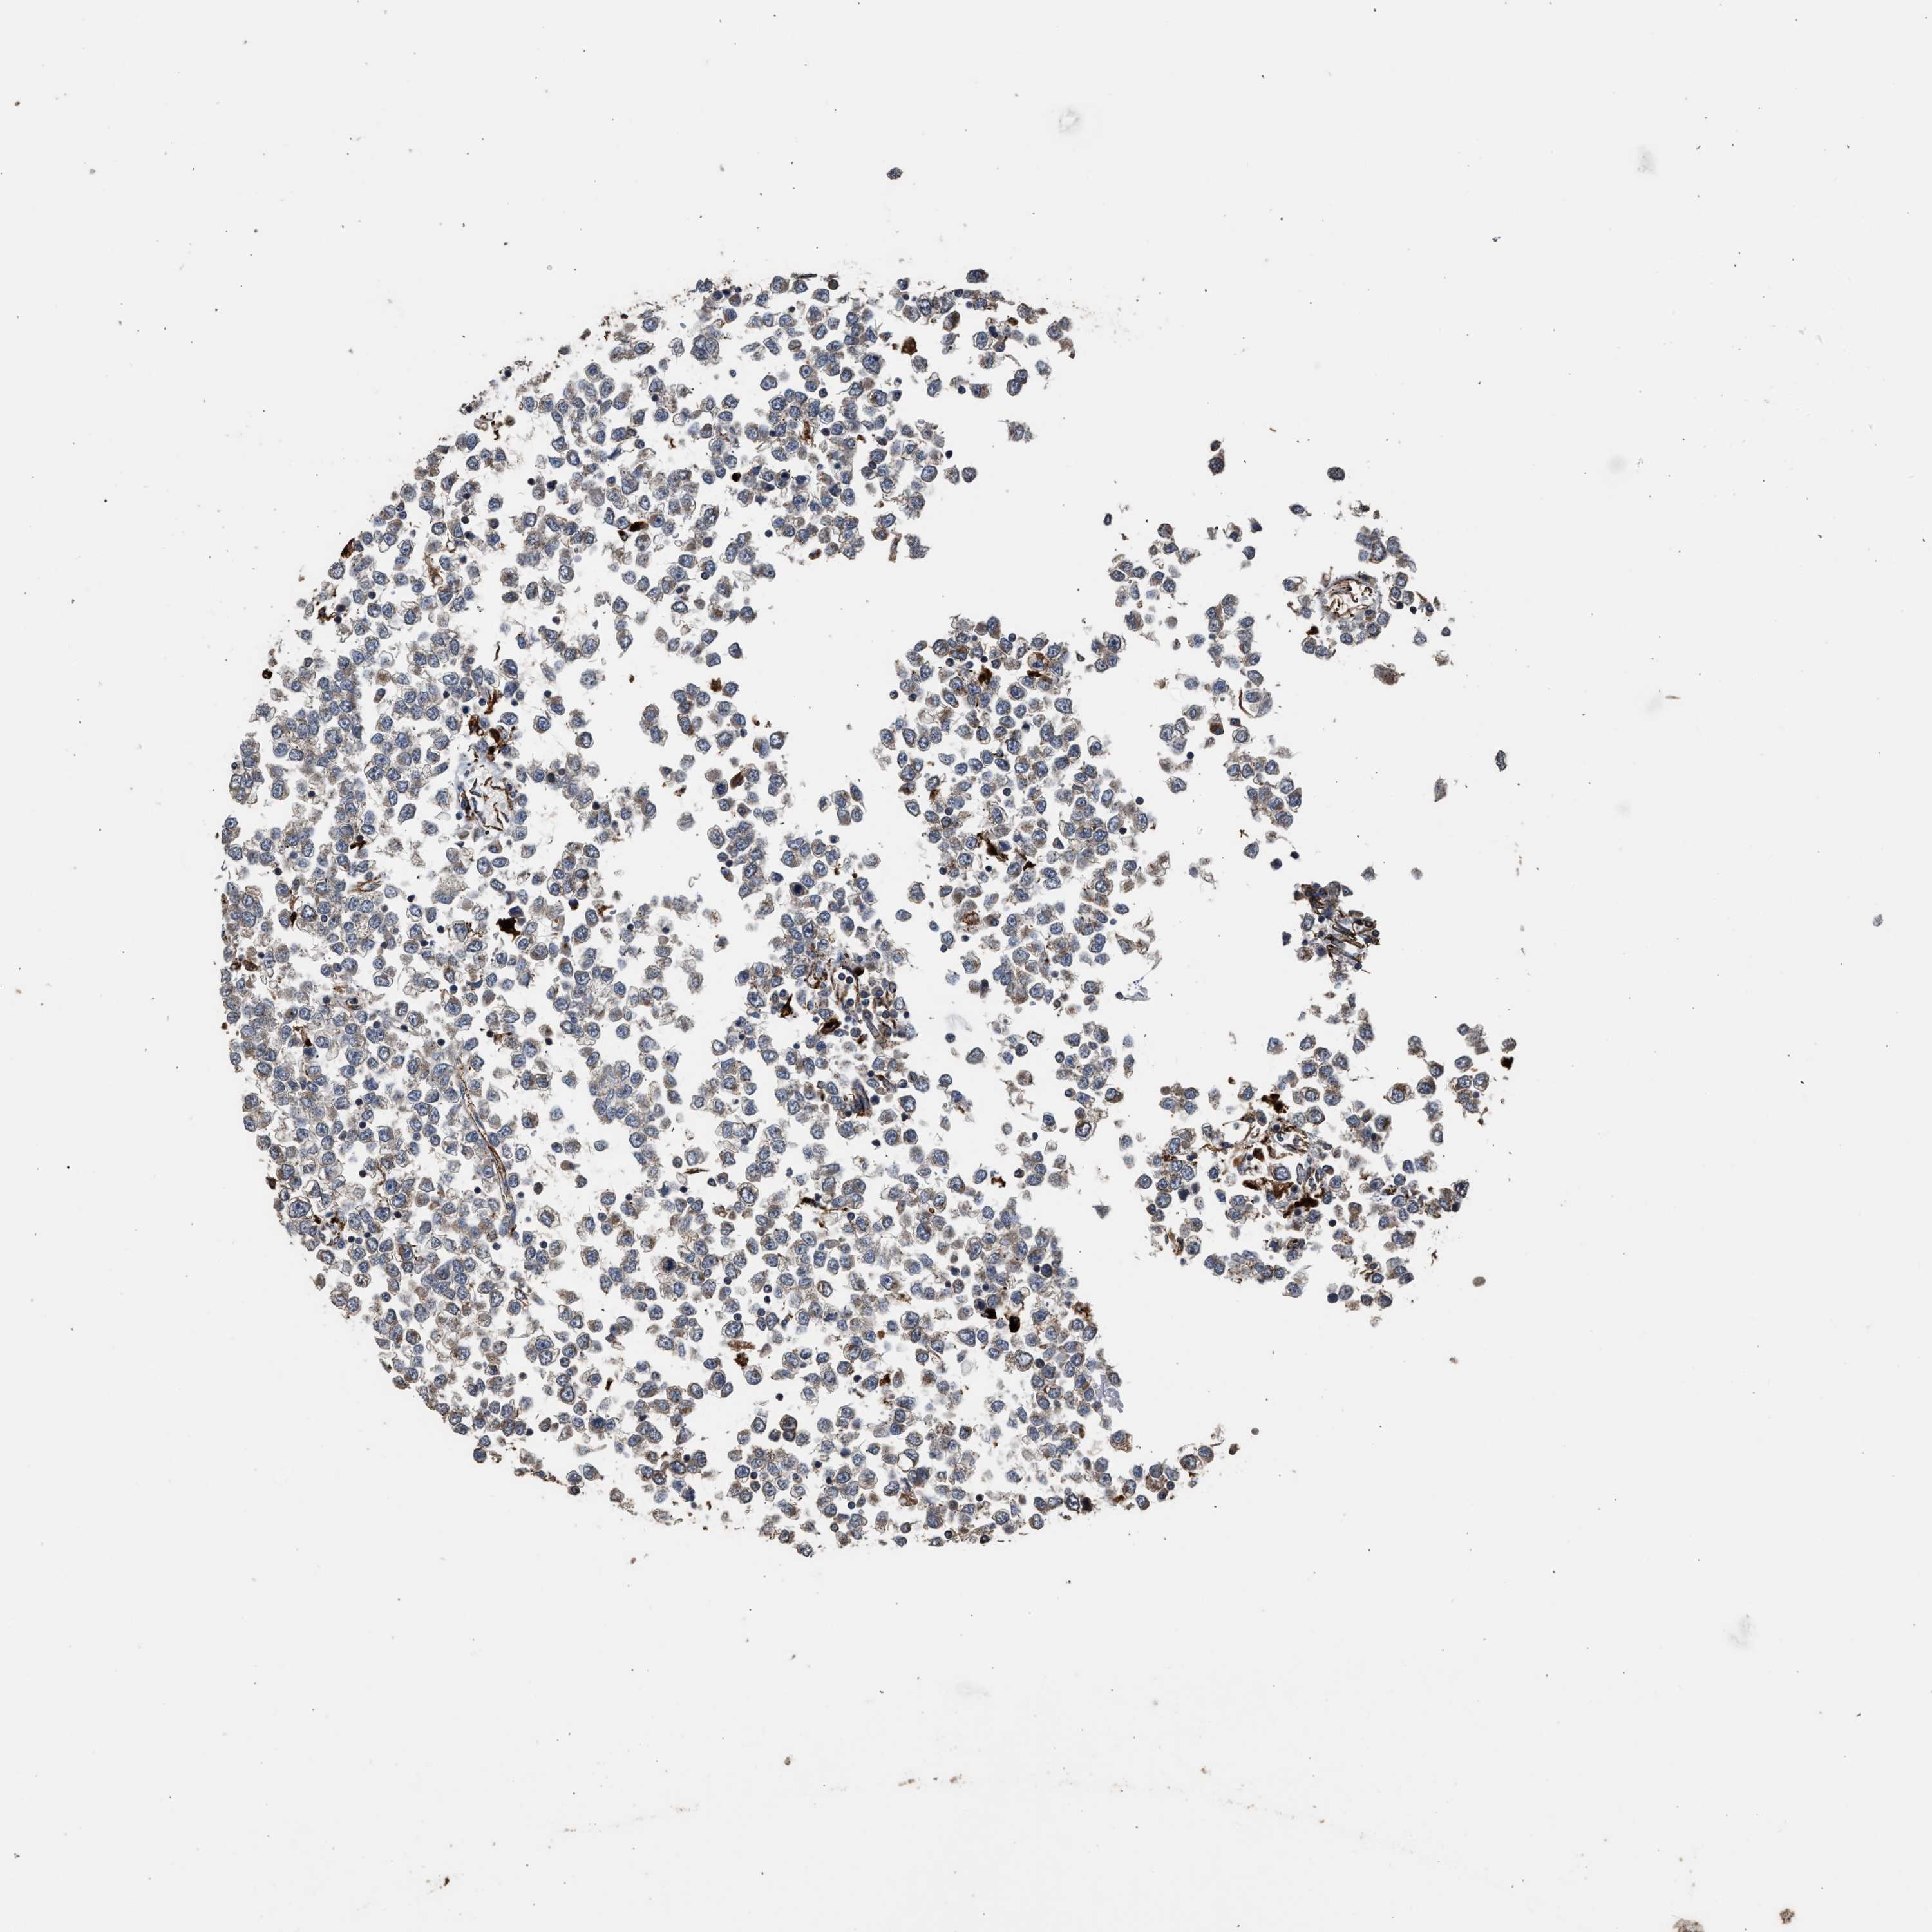

TESTIS CANCER - Protein expressioni

A mouse-over function shows sample information and annotation data. Click on an image to view it in a full screen mode. Samples can be filtered based on level of antibody staining by selecting one or several of the following categories: high, medium, low and not detected. The assay and annotation is described here.

Note that samples used for immunohistochemistry by the Human Protein Atlas do not correspond to samples in the TCGA dataset.

Antibody stainingi

Antibody staining in the annotated cell types in the current human tissue is reported as not detected, low, medium, or high, based on conventional immunohistochemistry profiling in selected tissues. This score is based on the combination of the staining intensity and fraction of stained cells.

Each image is clickable and will lead to virtual microscopy that enables deeper exploration of all samples and also displays staining intensity scores, fraction scores and subcellular localization as well as patient and tissue information for each sample.

Antibody CAB017112

Staining

High

Medium

Low

Not detected

Intensity

Strong

Moderate

Weak

Negative

Quantity

>75%

75%-25%

<25%

None

Location

Nuclear

Cytoplasmic/membranous

Cytoplasmic/membranous,nuclear

Carcinoma, Embryonal, NOS

Seminoma, NOS